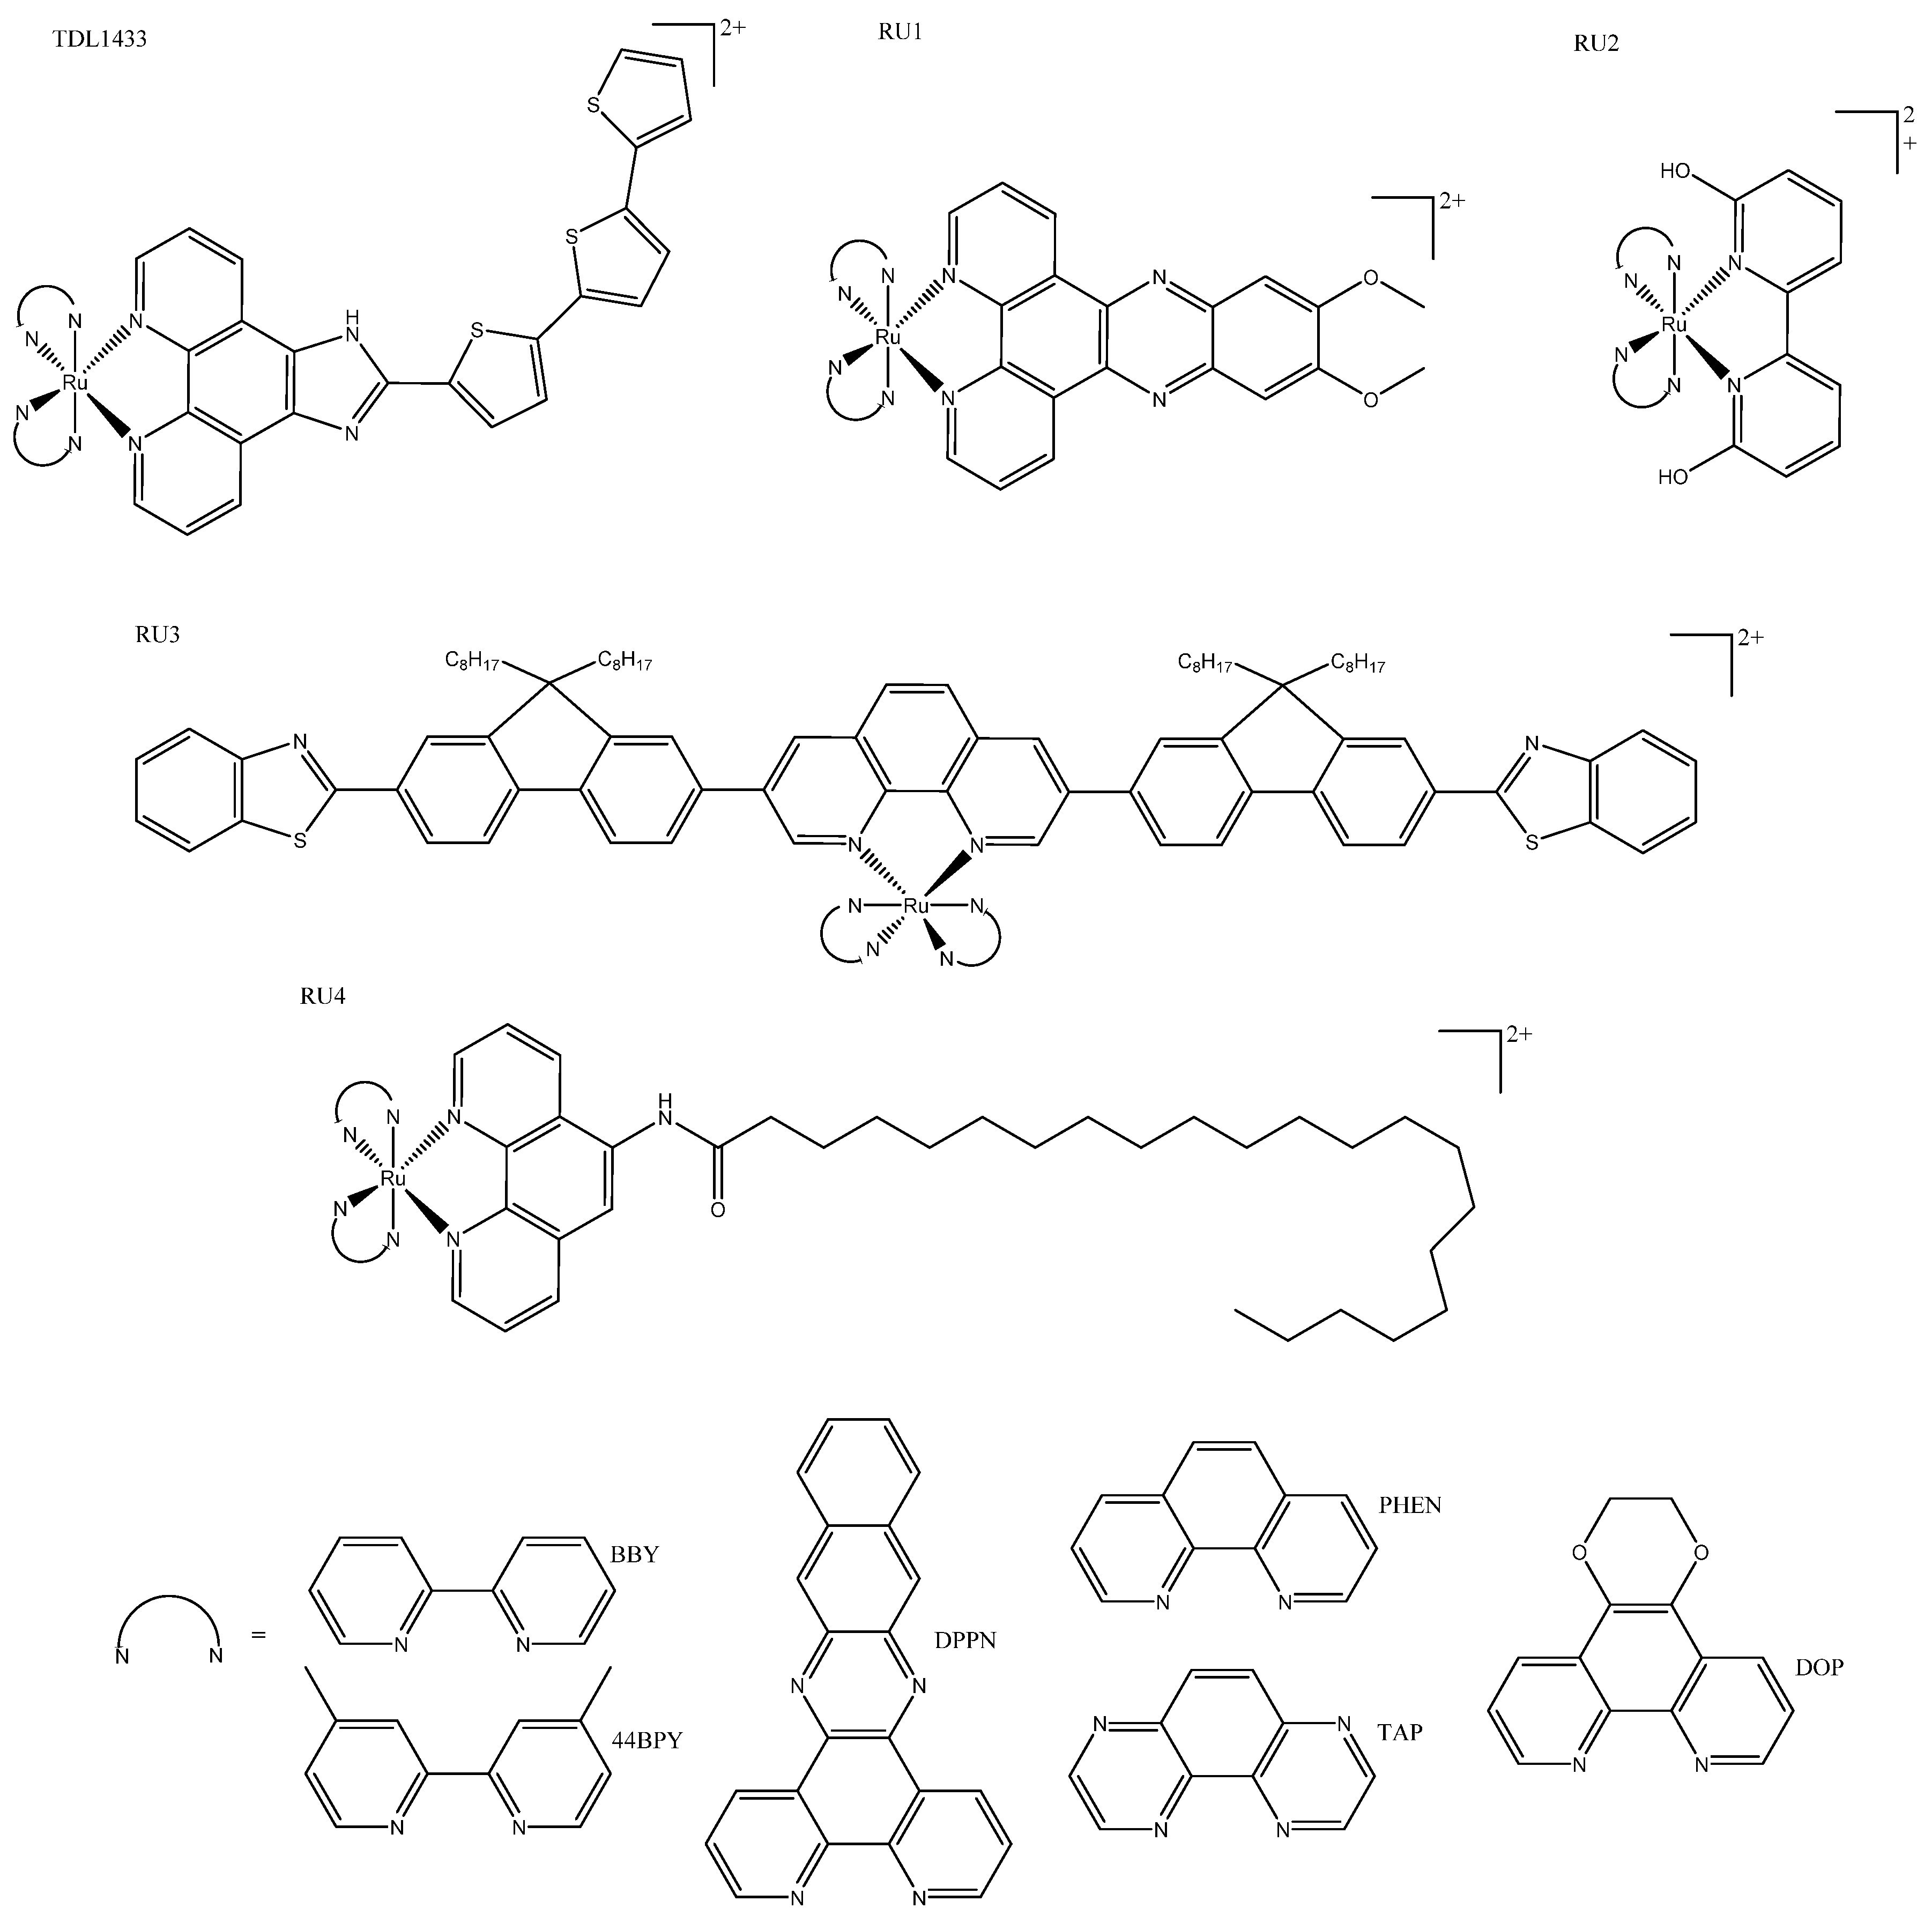

3. Ruthenium Complexes

3.1. Tris(bipyridine)ruthenium(II)-Inspired Complexes

3.2. Piano Stool Complexes

3.3. Cyclometallated/Diverse Coordination Sphere

3.4. Other

- Monro, S.; Colón, K.L.; Yin, H.; Roque, J.; Konda, P.; Gujar, S.; Thummel, R.P.; Lilge, L.; Cameron, C.G.; McFarland, S.A. Transition Metal Complexes and Photodynamic Therapy from a Tumor-Centered Approach: Challenges, Opportunities, and Highlights from the Development of TLD1433. Chem. Rev. 2019, 119, 797–828. [Google Scholar] [CrossRef]

- Hess, J.; Huang, H.; Kaiser, A.; Pierroz, V.; Blacque, O.; Chao, H.; Gasser, G. Evaluation of the Medicinal Potential of Two Ruthenium(II) Polypyridine Complexes as One- and Two-Photon Photodynamic Therapy Photosensitizers. Chem. Eur. J. 2017, 23, 9888–9896. [Google Scholar] [CrossRef]

- Qu, F.; Lamb, R.W.; Cameron, C.G.; Park, S.; Oladipupo, O.; Gray, J.L.; Xu, Y.; Cole, H.D.; Bonizzoni, M.; Kim, Y.; et al. Singlet Oxygen Formation vs. Photodissociation for Light-Responsive Protic Ruthenium Anticancer Compounds: The Oxygenated Substituent Determines Which Pathway Dominates. Inorg. Chem. 2021, 60, 2138–2148. [Google Scholar] [CrossRef]

- Wang, L.; Yin, H.; Jabed, M.A.; Hetu, M.; Wang, C.; Monro, S.; Zhu, X.; Kilina, S.; McFarland, S.A.; Sun, W. π-Expansive Heteroleptic Ruthenium(II) Complexes as Reverse Saturable Absorbers and Photosensitizers for Photodynamic Therapy. Inorg. Chem. 2017, 56, 3245–3259. [Google Scholar] [CrossRef]

- Estalayo-Adrián, S.; Blasco, S.; Bright, S.A.; McManus, G.J.; Orellana, G.; Williams, D.C.; Kelly, J.M.; Gunnlaugsson, T. Effect of Alkyl Chain Length on the Photophysical, Photochemical, and Photobiological Properties of Ruthenium(II) Polypyridyl Complexes for Their Application as DNA-Targeting, Cellular-Imaging, and Light-Activated Therapeutic Agents. ACS Appl. Bio Mater. 2021, 4, 6664–6681. [Google Scholar] [CrossRef]

- Lari, M.; Martínez-Alonso, M.; Busto, N.; Manzano, B.R.; Rodríguez, A.M.; Acuña, M.I.; Domínguez, F.; Albasanz, J.L.; Leal, J.M.; Espino, G.; et al. Strong Influence of Ancillary Ligands Containing Benzothiazole or Benzimidazole Rings on Cytotoxicity and Photoactivation of Ru(II) Arene Complexes. Inorg. Chem. 2018, 57, 14322–14336. [Google Scholar] [CrossRef]

- Srivastava, P.; Verma, M.; Kumar, A.; Srivastava, P.; Mishra, R.; Sivakumar, S.; Patra, A.K. Luminescent Naphthalimide-Tagged Ruthenium(II)-Arene Complexes: Cellular Imaging, Photocytotoxicity and Transferrin Binding. Dalton Trans. 2021, 50, 3629–3640. [Google Scholar] [CrossRef]

- Miachin, K.; Del Solar, V.; El Khoury, E.; Nayeem, N.; Khrystenko, A.; Appelt, P.; Neary, M.C.; Buccella, D.; Contel, M. Intracellular Localization Studies of the Luminescent Analogue of an Anticancer Ruthenium Iminophosphorane with High Efficacy in a Triple-Negative Breast Cancer Mouse Model. Inorg. Chem. 2021, 60, 19152–19164. [Google Scholar] [CrossRef]

- Ghosh, G.; Colón, K.L.; Fuller, A.; Sainuddin, T.; Bradner, E.; McCain, J.; Monro, S.M.A.; Yin, H.; Hetu, M.W.; Cameron, C.G.; et al. Cyclometalated Ruthenium(II) Complexes Derived from α-Oligothiophenes as Highly Selective Cytotoxic or Photocytotoxic Agents. Inorg. Chem. 2018, 57, 7694–7712. [Google Scholar] [CrossRef]

- McCain, J.; Colón, K.L.; Barrett, P.C.; Monro, S.M.A.; Sainuddin, T.; Roque Iii, J.; Pinto, M.; Yin, H.; Cameron, C.G.; McFarland, S.A. Photophysical Properties and Photobiological Activities of Ruthenium(II) Complexes Bearing π-Expansive Cyclometalating Ligands with Thienyl Groups. Inorg. Chem. 2019, 58, 10778–10790. [Google Scholar] [CrossRef]

- Zhang, Y.; Zhou, Q.; Tian, N.; Li, C.; Wang, X. Ru(II)-Complex-Based DNA Photocleaver Having Intense Absorption in the Phototherapeutic Window. Inorg. Chem. 2017, 56, 1865–1873. [Google Scholar] [CrossRef]

- Saeed, H.K.; Jarman, P.J.; Archer, S.; Sreedharan, S.; Saeed, I.Q.; Mckenzie, L.K.; Weinstein, J.A.; Buurma, N.J.; Smythe, C.G.W.; Thomas, J.A. Homo- and Heteroleptic Phototoxic Dinuclear Metallo-Intercalators Based on RuII(dppn) Intercalating Moieties: Synthesis, Optical, and Biological Studies. Angew. Chem. 2017, 56, 12628–12633. [Google Scholar] [CrossRef]

- Zhao, Z.; Hu, R.; Shi, H.; Wang, Y.; Ji, L.; Zhang, P.; Zhang, Q. Design of Ruthenium-Albumin Hydrogel for Cancer Therapeutics and Luminescent Imaging. J. Inorg. Biochem. 2019, 194, 19–25. [Google Scholar] [CrossRef]

- Mascheroni, L.; Dozzi, M.V.; Ranucci, E.; Ferruti, P.; Francia, V.; Salvati, A.; Maggioni, D. Tuning Polyamidoamine Design to Increase Uptake and Efficacy of Ruthenium Complexes for Photodynamic Therapy. Inorg. Chem. 2019, 58, 14586–14599. [Google Scholar] [CrossRef]

- Yang, J.; He, X.; Ke, Z.; Chen, J.; Zou, Z.; Wei, B.; Zou, D.; Zou, J. Two Photoactive Ru (II) Compounds Based on Tetrazole Ligands for Photodynamic Therapy. J. Inorg. Biochem. 2020, 210, 111127. [Google Scholar] [CrossRef]

- Nehru, S.; Veeralakshmi, S.; Kalaiselvam, S.; Subin David, S.P.; Sandhya, J.; Arunachalam, S. DNA Binding, Antibacterial, Hemolytic and Anticancer Studies of Some Fluorescent Emissive Surfactant-Ruthenium(II) Complexes. J. Biomol. Struct. Dyn. 2021, 39, 2242–2256. [Google Scholar] [CrossRef]

- Zhao, Z.; Zhang, X.; Li, C.-E.; Chen, T. Designing Luminescent Ruthenium Prodrug for Precise Cancer Therapy and Rapid Clinical Diagnosis. Biomaterials 2019, 192, 579–589. [Google Scholar] [CrossRef]

- Li, H.; Xie, C.; Lan, R.; Zha, S.; Chan, C.-F.; Wong, W.-Y.; Ho, K.-L.; Chan, B.D.; Luo, Y.; Zhang, J.-X.; et al. A Smart Europium-Ruthenium Complex as Anticancer Prodrug: Controllable Drug Release and Real-Time Monitoring under Different Light Excitations. J. Med. Chem. 2017, 60, 8923–8932. [Google Scholar] [CrossRef]

- Dos Santos, J.S.; Ramos, L.C.; Ferreira, L.P.; Campo, V.L.; de Rezende, L.C.D.; da Silva Emery, F.; Santana da Silva, R. Cytotoxicity, Cellular Uptake, and Subcellular Localization of a Nitrogen Oxide and Aminopropyl-β-Lactose Derivative Ruthenium Complex Used as Nitric Oxide Delivery Agent. Nitric Oxide Biol. Chem. 2019, 86, 38–47. [Google Scholar] [CrossRef]

- Weynand, J.; Diman, A.; Abraham, M.; Marcélis, L.; Jamet, H.; Decottignies, A.; Dejeu, J.; Defrancq, E.; Elias, B. Towards the Development of Photo-Reactive Ruthenium(II) Complexes Targeting Telomeric G-Quadruplex DNA. Chemistry 2018, 24, 19216–19227. [Google Scholar] [CrossRef]

| TDL1433 | 137 ± 3 | 1.9 ± 0.1 (400-700) | 525 | Optimized clinical procedure and completion of human clinical trials. | |||

| RU1 | 36.5 ± 3.0 | 3.1 ± 0.6 (420) | 620 | 420 | Photosensitizers for one- and two-photon PDT. | ||

| RU3 | 123 ± 3.62 | 3.77 ± 0.18 | 557/640 | 413 | Activated at multiple wavelengths; tracking possible both before and after photo treatment. | ||

| RU4a | 13 ± 2 | 0.47 ± 0.01 ** | 614 | 440 | Shows how modification of ancillary ligand and lipophilicity enhances therapeutic effect. | ||

| RU4b | 11 ± 3 | 2 ± 1 ** | 643 | 418 | |||

| RU6 | 83.1 ± 6.2 * | 34.1 ± 2.4 (460) | 500 | 355 | Slight variations in structure led to phototoxic or other photoactivated complexes. | ||

| RU6 | 31.3 ± 4.5 | 11.5 ± 2.5 (488) | 534 | 440 | Tagged with napthalamide derivative to target DNA. | ||

| RU8a | >300 | 12.0 ± 0.4 (633) | 805 | 540 | More lipophilic and absorption; more red-shifted than their non-cyclometallated counterparts. | ||

| RU8b | >300 | 16.6 ± 1.53 (625) | 728 | 550 | |||

| RU16 | 277.0 ± 7.1 | 32.5 ± 8.2 (488) | 570-750 | 350 | The linker could be irradiated at different wavelengths for different functionalization (prodrug activation or fluorescence). | ||